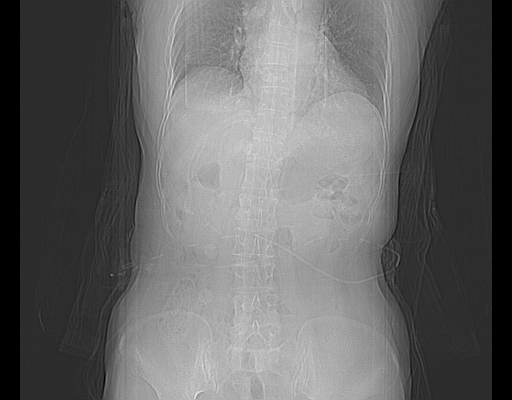

2008-6-10ct平扫

ct增强

2008-11-10ct平扫(其间去中山医院诊治未行特殊治疗)

考虑为肝血管瘤破裂出血并肝包膜下血肿;右侧少量胸腔积液。

1)考虑肝癌破裂出血并包膜下血肿;不排除肝腺瘤破裂出血可能。2)肝左叶外侧段囊肿。3)慢性胆囊炎。4)右侧少量胸腔积液。